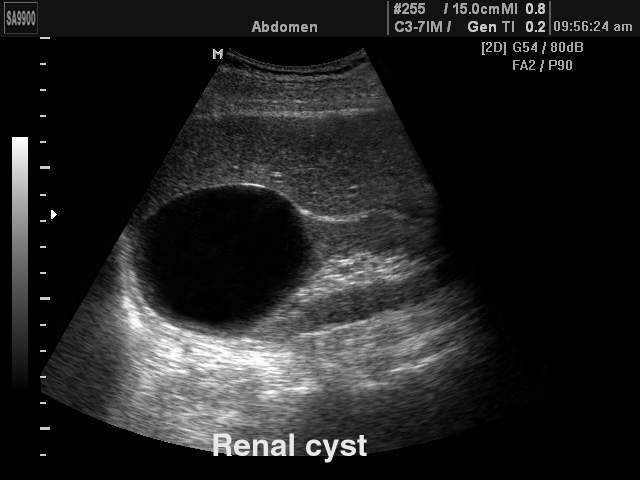

Describe the Pathology seen in the right kidney (Use sonographic terminology)

Anechoic (Renal Cyst)